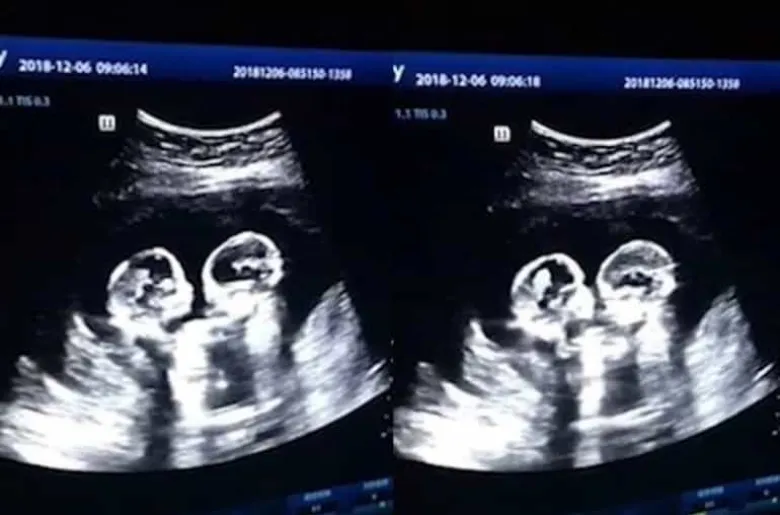

Ուլտրաձայնային հետազոտությունը ֆիքսել է՝ ինչպես են երկվորյակները «կռվում» մայրական արգանդում (տեսանյութ)

Բրիտանական Daily Mail պարբերականը հրապարակել է ուշագրավ տեսանյութ, որն արվել է հղի չինուհու որովայնային խոռոչի ուլտրաձայնային հետազոտության ժամանակ ու ներկայացնում է միաբջիջ երկվորյակների՝ մայրական արգանդում «կռվելու» պահը:

Տեսանյութն արվել է հղիության չորրորդ ամսում: Դրանում երևում է՝ ինչպես են պտուղներն իրար հարվածում թաթիկներով:

«Այնքան զավեշտալի էր տեսնել՝ ինչպես են դեռևս չծնված դուստրերս բռնցքամարտով զբաղվում: Եվ ես ամենևին էլ չէի ակնկալում, որ նրանք նախքան ծնվելն արդեն համացանցի աստղեր են լինելու»,-ասել է 28-ամյա հայրը:

Տղամարդը մանրամասնել է, որ երեխաներն արդեն ծնվել են ու միանգամայն առողջ են:

Ինչ վերաբերում է ուշագրավ տեսանյութին, ապա այն համացանցում ունի ավելի քան 2,5 մլն հավանում, 80 000-ից ավելի մեկնաբանություն: